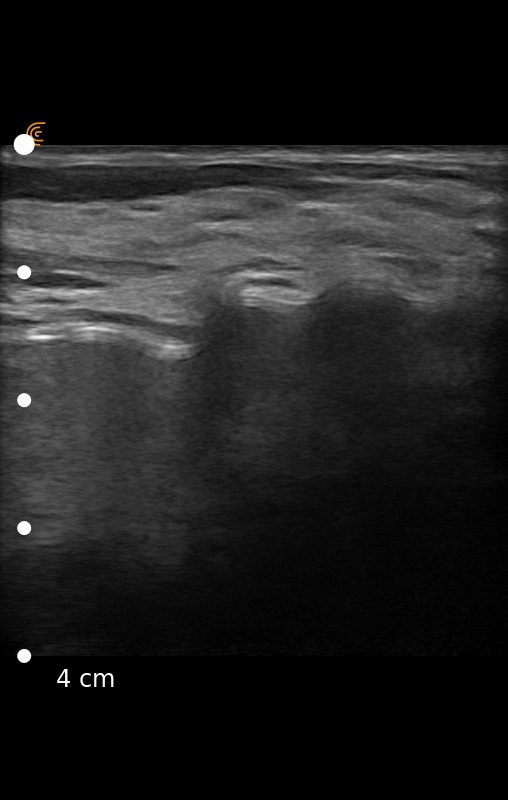

According to the FDA, ultrasound is an indispensable tool for plastic surgeons, for example, to regularly screen patients to detect silent ruptures.1 Dr. Roldan agrees. He recently shared ultrasound images captured on a patient with a ruptured silicon gel breast implant using the Clarius L7 HD Scanner. Can you identify the ruptured implant?

The right image clearly shows the stepladder sign, which are horizontally stacked echogenic lines traversing through the implant. Dr. Roldan confirmed the intracapsular rupture during the explantation surgery. The left ultrasound image includes a normal scan of the left breast.